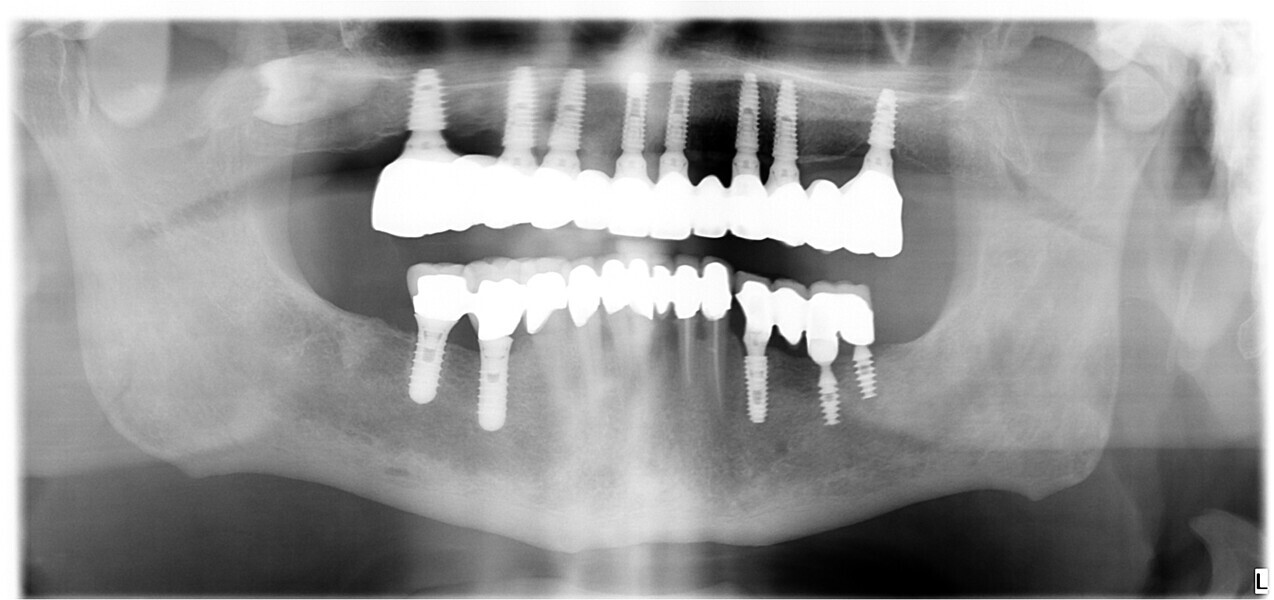

At the initial visit, digital impressions were captured using the Medit i700 scanner to document the residual teeth, soft tissue, existing prosthesis and opposing arch. The occlusal records were obtained at the current vertical dimension of occlusion and in centric relation. Mandibular movements were recorded with the zebris JMA jaw registration system (zebris Medical). Intra- and extra-oral photographs were also taken. A virtual diagnostic wax-up and a digital smile simulation were created based on these records (Smile Creator, exocad). Finally, eight implants were planned (Figs. 3 & 4) according to the new wax-up (exoplan 3.1, exocad), and both a surgical guide and a metal-reinforced temporary prosthesis were fabricated in advance (Figs. 5–7).

On the day of surgery, local anaesthesia was administered, and the first surgical guide was stabilised on the remaining teeth to prepare five anchor pin sites. The compromised teeth were then extracted, and a second surgical guide was secured at the prepared pin sites. Eight implants (Osstem TSIII SOI, Osstem Implant) were placed, five in immediate post-extraction sites and three in previously healed areas. All the placements were fully guided using a surgical guide without metallic sleeves and a dedicated surgical kit (OneGuide KIT, Osstem Implant; Fig. 8).11 One implant required a crestal sinus lift, which was performed using a fully guided approach (OneCAS KIT, Osstem Implant; Fig. 9). Xenograft bone material (A-Oss, Osstem Implant) was used to fill the extraction sockets and the sinus cavity.12 Multi-unit abutments and temporary abutments (Osstem Implant) were immediately placed on all the implants, according to the one abutment, one time concept.13 A prefabricated PMMA-based temporary prosthesis with metal reinforcement was delivered and immediately fixed in the mouth. Chairside adjustments were made to refine the prosthesis and ensure proper occlusion (Figs. 10–12). The patient received postoperative instructions and medication.

Four months later, digital impressions were taken using the Medit i900. These included an impression of the functional temporary prosthesis, an impression of the soft-tissue anatomy and an impression with custom-designed scan bodies, featuring lateral extensions to enhance intra-oral scan accuracy (SmartFlag, APOLLO; Fig. 13). A novel digital workflow, named Medit SmartX (Medit Link Version 3.4.2), was utilised (Fig. 14). This system enables real-time recognition and alignment of scan body libraries, enhancing predictability, efficiency and safety of full-arch digital impressions. A combination of scanning techniques was applied to increase the final accuracy: straight and zigzag in the anterior regions and straight in the posterior regions.14

At the final appointment, the definitive hybrid screw-retained prosthesis was delivered. The definitive prosthesis consisted of a CAD/CAM titanium framework screwed on to all of the implants and three monolithic zirconia prosthetic segments bonded on top (Figs. 18a–c). The occlusion was evaluated, and the patient was enrolled in a four-month maintenance programme. At the last follow-up (one year after implant placement), all of the implants were successful and the patient was fully satisfied with the new prosthesis (Figs. 19–22).

Another critical factor that influences long-term clinical outcomes is the 3D positioning of implants. Accurate implant placement in terms of depth, angulation and mesiodistal spacing directly affects prosthetic fit, occlusal harmony and load distribution.17 In the edentulous maxilla—where anatomical constraints and soft-tissue mobility challenge manual techniques—the use of computer-guided surgery proves especially valuable. In this case, fully guided implant placement was facilitated by digital planning and a 3D-printed surgical guide anchored by pins.18 This protocol enabled a minimally invasive approach and the execution of a crestal sinus lift, illustrating how guided surgery can manage anatomical complexity with minimal invasiveness. The precision afforded by virtual planning translates directly into surgical accuracy, improving both prosthetic predictability and patient outcomes.19